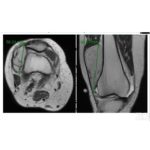

Oncology for the FRCS Tr and Orth

To crack any bone tumor and its prognosis we need to focus on mainly 5 points First we look for which bone is involved for Example femur, tibia etc and later we look for the location of the particular bone involved such as physis, metaphysis, epiphysis, diaphysis etc. Along with these we classify it as […]